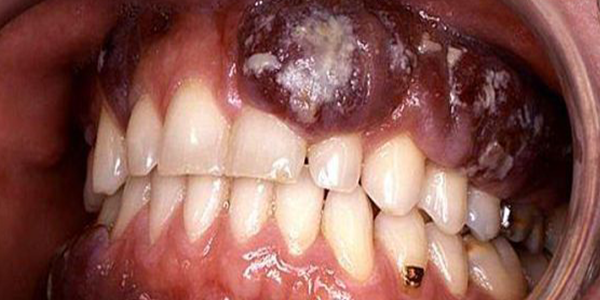

سرطان لثه چیست؟

همانطور که میدانید به تکثیر بیرویه سلولها، سرطان میگویند. در سرطان لثه، هم سلولهای لثه بالایی و هم پایینی بیش از اندازه تقسیمات سلولی انجام میدهند. سرطان لثه یا همان سرطان دهان بیشتر در آقایان و افراد مسن دیده میشود.

از مهمترین عوامل سرطان لثه مصرف دخانیات و به طور کلی دود حاصل از تنباکو است. تشخیص زود هنگام این بیماری بسیار اهمیت دارد و در صورت تشخیص و درمان به موقع درمان موفقیتآمیز را به همراه خواهد داشت.